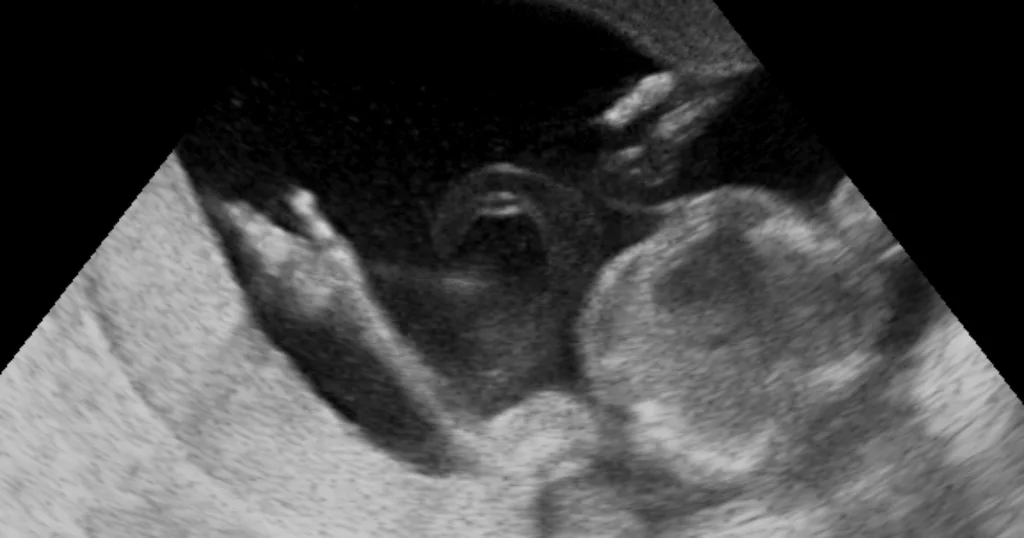

Dávali mu šanci na přežití 1 : 1 000 000. Při porodu se stalo něco, co popřelo zákony moderní medicíny

Porod dítěte nemusí být vždy radostnou záležitostí, která probíhá bez problémů. To byl také případ tohoto páru, dokud se nestal skutečný zázrak. Nick Schnarr a jeho manželka Brooklyn se po dlouhé měsíce těšili, až budou [...]...